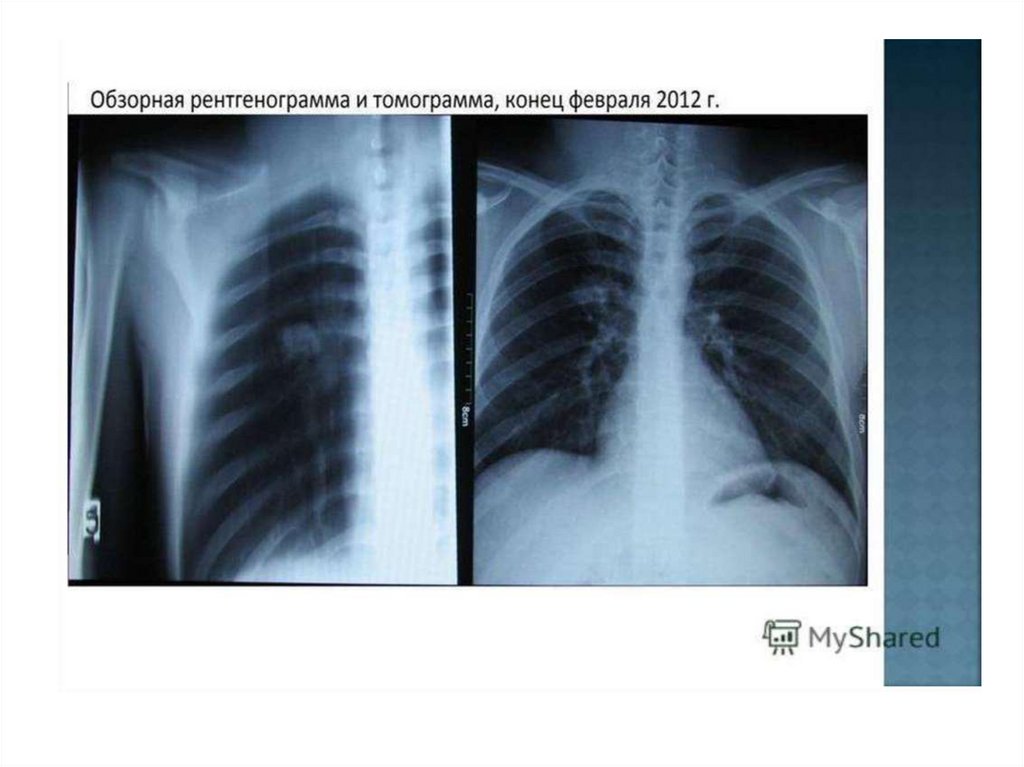

Рентгенограмма № 2

31. Рентгенограмма № 2